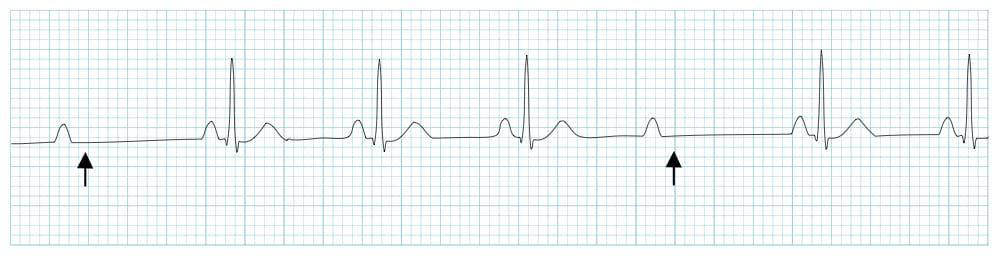

First-degree AV block is defined as a prolonged PR interval >0.20 seconds (>5 small boxes) with 1:1 AV conduction - every P wave is followed by a QRS complex.

Figure 1: First-degree AV block showing consistent PR interval prolongation. Source: LITFL

Critical distinction: First-degree AV block = prolonged but consistent PR interval. If the PR progressively lengthens until a QRS is dropped, that's second-degree Mobitz I (Wenckebach). If the PR is constant but QRS complexes are intermittently dropped, that's Mobitz II.